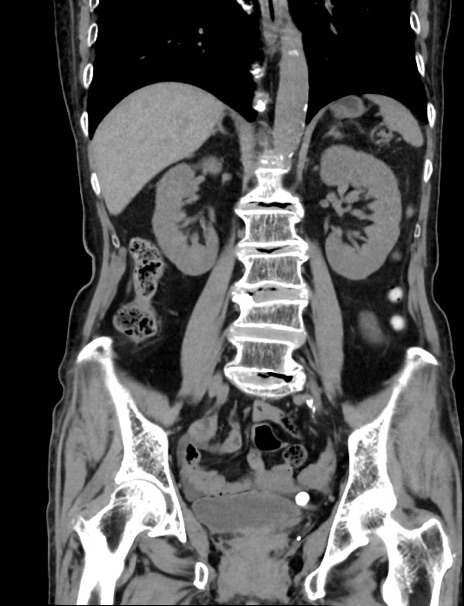

症例33(冠状断像)

【症例】70歳代 女性

【主訴】心窩部痛

【現病歴】延髄病変の精査・加療にて神経内科入院中。本日より心窩部痛あり。

【身体所見】右下腹部を中心に圧痛と反跳痛あり。

【データ】WBC 10900、CRP 0.02